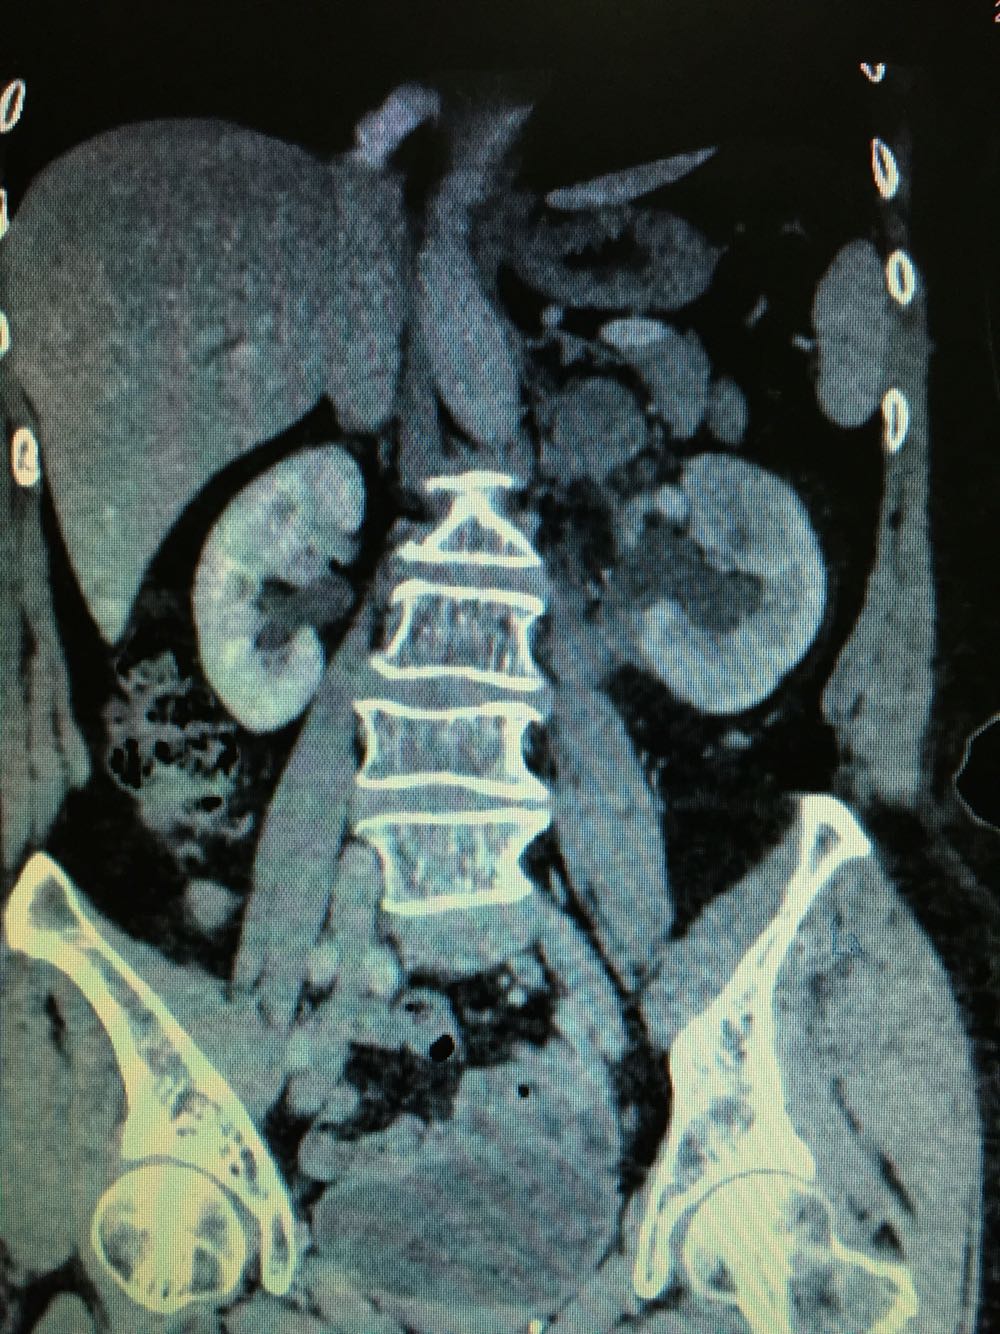

CT提示,左侧肾门处雪人样占位,包裹左肾静脉,左肾积水,与胰腺及左肾关系密切,血常规,肝肾功未见明显异常,GFR左侧27,右侧58。

诊断,左侧腹膜后占位:淋巴瘤?或者淋巴样增生?,侵犯周围器官组织?